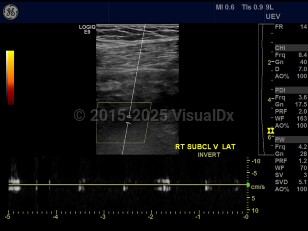

Subclavian vein thrombosis

A blood clot occurring in the subclavian vein, which leads to the brachiocephalic vein and the heart. Thrombi occur more commonly in the right side. Symptoms are primarily pain and edema of the upper extremity, neck, and face. Pulmonary emboli are a life-threatening complication of subclavian vein thrombosis. Many cases are associated with use of a central venous catheter. Other predisposing factors include hypercoagulable disorders and malignancy. Paget-von Schroetter syndrome is a rare cause of subclavian vein thrombosis. It presents in young, healthy patients after exercise. It is caused by a narrow thoracic outlet. Treatment typically consists of anticoagulation, extremity elevation, and local heat application.

Subclavian vein thrombosis